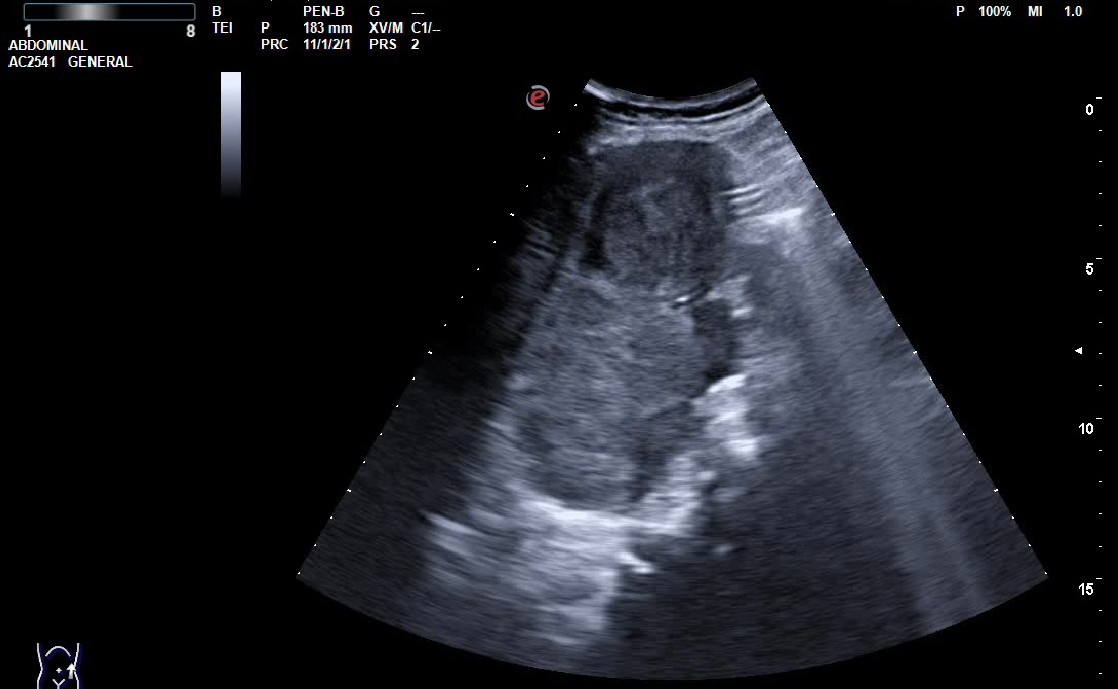

Hallazgos ecográficos

Se realiza ecografía en el Centro de Salud, donde se observa una masa de 123 x 102 x 103 mm de ecogenicidad mixta, con algunas áreas calcificadas en su interior, puntiformes, con bordes lobulados bien definidos, sin captación vascular. Se manda imágenes a Radiología mediante e-consulta y tramitan TAC abdominal, donde se confirma la masa de 12 cm de diámetro, siendo GIST la primera opción diagnóstica, a valorar proceso linfoproliferativo o sarcoma retroperitoneal.